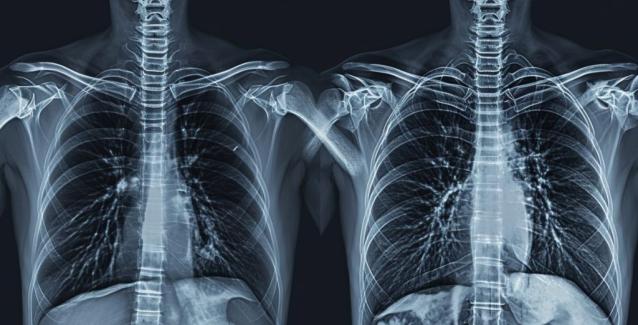

Ωστόσο, πολλοί μπορεί να αναπτύξουν και πόνο στο στήθος μαζί με τον βήχα, κάτι που μπορεί να συμβεί λόγω καταστάσεων που επηρεάζουν τους πνεύμονες, όπως η οξεία βρογχίτιδα και η πνευμονία.

2. Πνευμονία

Η πνευμονία είναι μια μόλυνση των αερόσακων στους πνεύμονες. Η μόλυνση μπορεί να είναι βακτηριακή, ιογενής ή μυκητιασική.

Η πνευμονία οδηγεί σε αυξημένο πύον και υγρό στους πνεύμονες, που μπορεί να προκαλέσει βήχα. Ο επίμονος βήχας, με τη σειρά του, μπορεί να προκαλέσει πόνο στο στήθος.